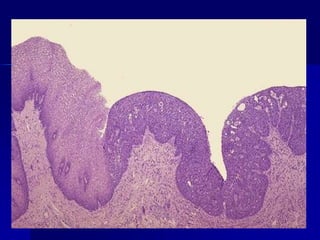

Epitelio superficial de la mucosa endocervical, que muestra células atípicas, con

su polaridad perdida, con variaciones en el tamaño, forma, disposición y

coloración de sus núcleos. No hay signos de infiltración del estro

Carcinoma escamoso

invasor.

Imagen microscópica a mediano aumento de un carcinoma escamoso invasor.

Obsérvese la presencia de nidos de márgenes irregulares, rodeados por estroma

desmoplásico. Dichos nidos están formados por células atípicas, con diferenciación

escamosa. Focalmente se evidencia alguna disqueratosis. Tinción de H-E,100X.

Adenocarcinoma "in situ". Epitelio superficialde la mucosa endocervical, que muestra células atípicas, con su polaridad perdida, con variaciones en el tamaño, forma, disposición y coloración de sus núcleos. No hay signos de infiltración del estro

Carcinoma escamoso invasor. Imagen microscópicaa mediano aumento de un carcinoma escamoso invasor. Obsérvese la presencia de nidos de márgenes irregulares, rodeados por estroma desmoplásico. Dichos nidos están formados por células atípicas, con diferenciación escamosa. Focalmente se evidencia alguna disqueratosis. Tinción de H-E,100X.